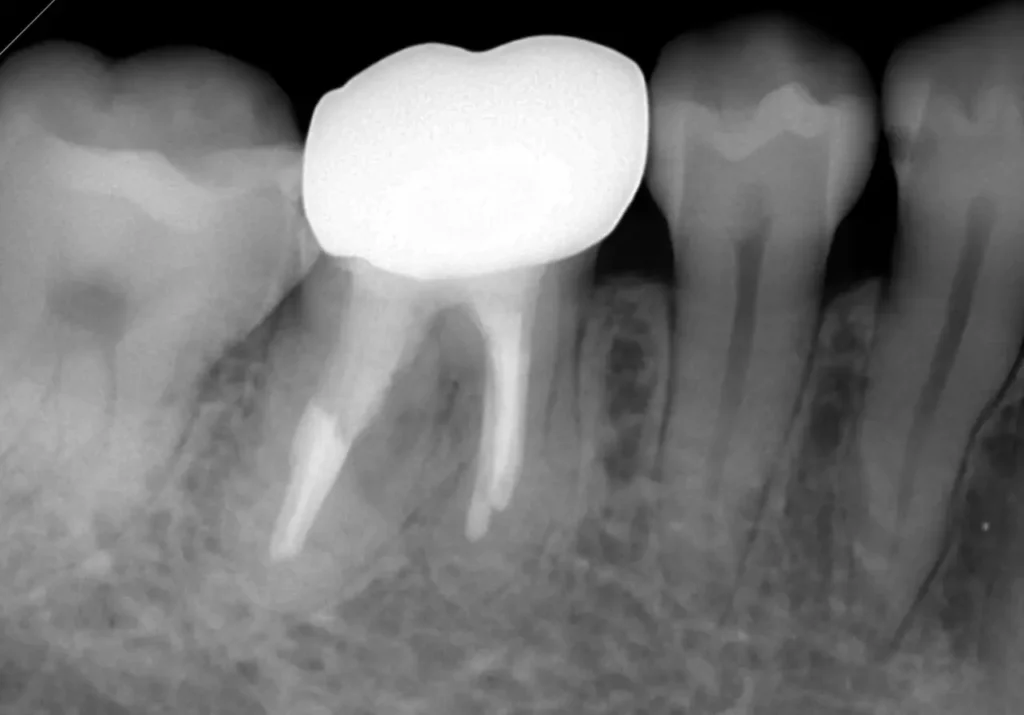

術後2年後レントゲン写真

根の周りの黒い影がなくなり、骨もほとんど回復して、痛みもありません